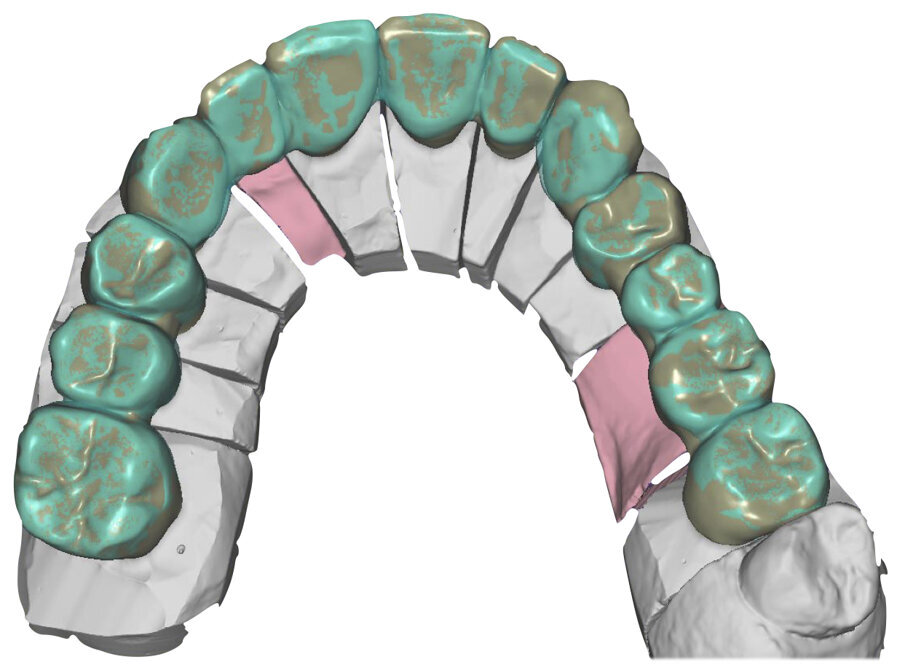

Ciò consente un miglioramento dei rapporti interarcata, un guadagno di spazio protesico in regioni premolari e molari, ed il mantenimento di uno spazio protesico conforme ad una corretta anatomia per i denti vitali da 1.3 a 2.3. Al paziente viene pertanto aggiornato il piano di trattamento e proposta la riabilitazione in TRP, con la previsione di overlays all’arcata inferiore per costruzione del nuovo piano occlusale. In posizione terapeutica sono modellati i coni delle centriche attive sui monconi sfilabili all’arcata inferiore, per la successiva individuazione al CAD con modulo articolatore del piano occlusale studiato. Questo rapporto articolare in TRP è ora scansito con scanner da laboratorio Xanos Evo Scan Compact (Fig. 24).

I modelli sono così importati in corretta posizione spaziale tramite il modulo exocad Virtual Articulator (Fig. 25). Non avendo a disposizione nel CAD l’analogo virtuale dell’articolatore Reference SL, viene impostato il sistema virtuale SAM, che usa lo stesso piano di riferimento axio-orbitale e geometria sovrapponibile al Reference SL. Per la programmazione virtuale dei parametri funzionali dell’articolatore si riesegue l’output dall’axiografia elettronica con Gamma Dental per SAM (Fig. 26). Si procede perciò ora con la modellazione CAD della ceratura mantenendo il riferimento dato dal piano occlusale individuato dai coni di centrica scansiti con l’articolatore (Fig. 27). L’articolatore virtuale consente una prima verifica dei rapporti occlusali tra gli elementi e un abbozzo di funzionalizzazione delle cuspidi con strumenti virtuali dinamici, che permette di arrivare ad un CAD design vicino alla morfologia ricercata (Figg. 28-33). Il modellato è ora fresato in cera Yeti Dental al CAM con fresatore VHF Cam5-S1 ed i denti in cera, tutti singolarmente sfilabili, sono posizionati sui modelli eseguiti con stampa 3D.

Il fresato ottenuto è poi riportato su articolatore Reference SL – già opportunamente programmato – e viene dall’Odontotecnico competente più precisamente funzionalizzato secondo i criteri della programmazione funzionale sequenziale, evidenziando con cere colorate i rapporti di centrica, le funzioni di mediotrusiva e protrusiva e le protezioni retrusive. I monconi sfilabili consentono la modellazione della sequenzialità mediotrusiva con la guida incisale indicata dalla registrazione axiografica (blu) (Figg. 34-37). La ceratura sequenziale è ora scansita con Sirona InEos X5 su Exocad, ed il modellato viene ricontrollato al CAD per spessori, connessioni e morfologia, e nella regolazione degli offsets per la ripreparazione dei monconi, ed è inviato al CAM per la fresatura dei II provvisori in Bredent breCAM.multicom, un PMMA con microriempitivo ceramico ad alta stabilità, su Dental Plus 5 Axis Milling Machine. La rifinitura dei monconi è seguita da ribasatura dei II provvisori in TRP - previo isolamento di tutte le superfici funzionali - e gli stessi sono poi rifiniti e lucidati. I soli elementi 3.3, 4.2 e 4.3 sono rimodellati in regione incisale con addictions in composito, secondo la morfologia studiata in ceratura. La consegna conferma la buona integrazione dei manufatti dal punto di vista estetico, occlusale, articolare e neuromuscolare, con controllo occlusale conforme al progetto (Figg. 38-42).